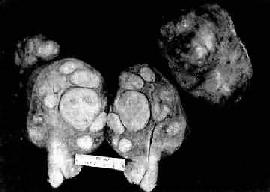

图13-7 子宫平滑肌

多个肌结节,位于肌壁内、粘膜下及浆膜下,境界分明,宫腔受挤压呈裂隙状